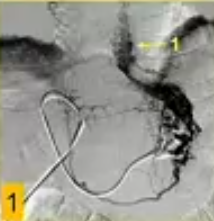

![]() ![]() US引导下经皮进入门静脉分支(瘤栓远端周围静脉),随后在瘤栓“上方”进行门静脉造影;

由于导管通过瘤栓,在血栓“下方”进行门静脉造影。

门静脉手术细节:使用5或8F直径的双极射频装置(HabibTM EndoHPB, EMcision Ltd., London, UK),施加10-15瓦的功率,持续2分钟,该装置通过导管定位到PV血栓中